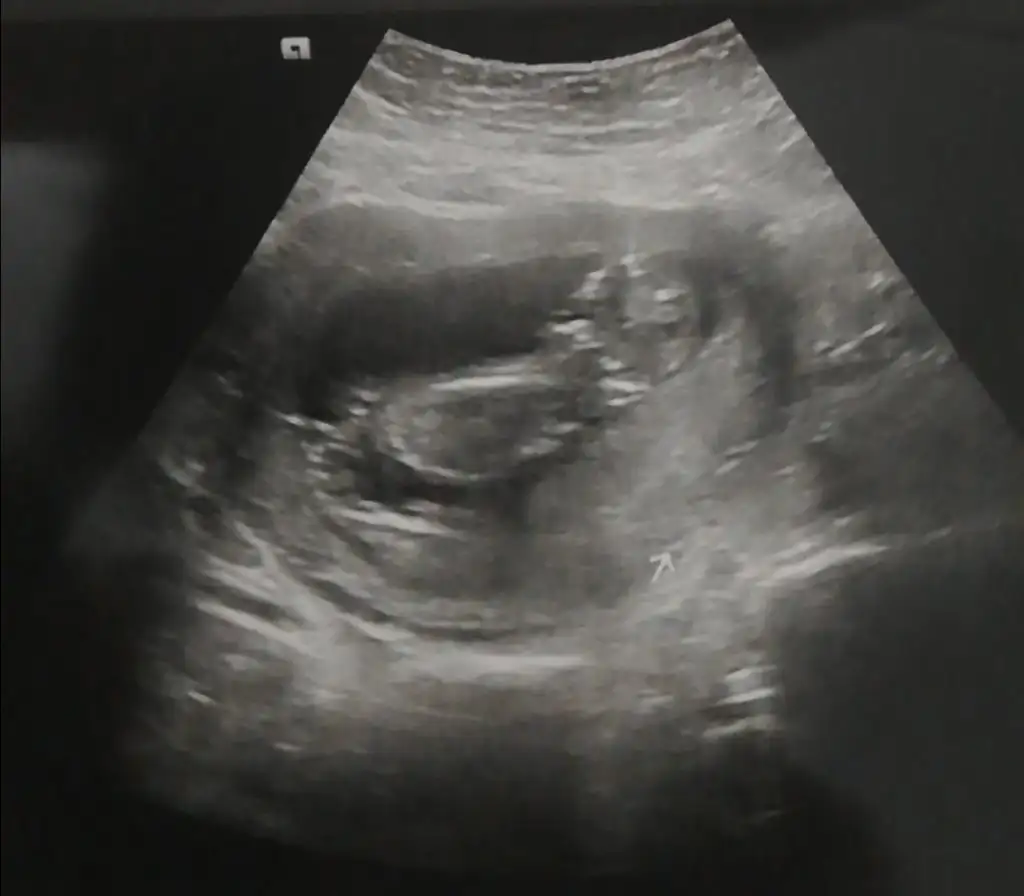

Erkek ve kız için 11 + 12+ yada 13 hafta usg görüntüsü olmalı açıklamalar asagıda yazıyorrabbim herkesin gönlüne göre nasip etsin inşallah .. ecmain

[/B]Eki Görüntüle 473828 gordugunuz gibi ust taraftaki simgedende anlasildigi gibi eger cikinti paralel ise kiz

yok 30°lik bir aciyla yukari dogru bakiyorsa %99 oglunuz olacak demektir simdi bi kac ornek resimler daha koyacagim kiziminkide dahil

Eki Görüntüle 473831 simdi burada cikintilara bakin eger bel popo cizgisine paralel ise kiz

yok 30 derecelik bir aciyla yukari bakiyorsa erkek

yabancilarin hepsi biliyor bunu biz neden eksik kalalim gayet bilimsel simdi ellerinde11 12 13 ultrason fotografi olanlar alsin hemen baksin yada koyalim buraya yorumlayalim